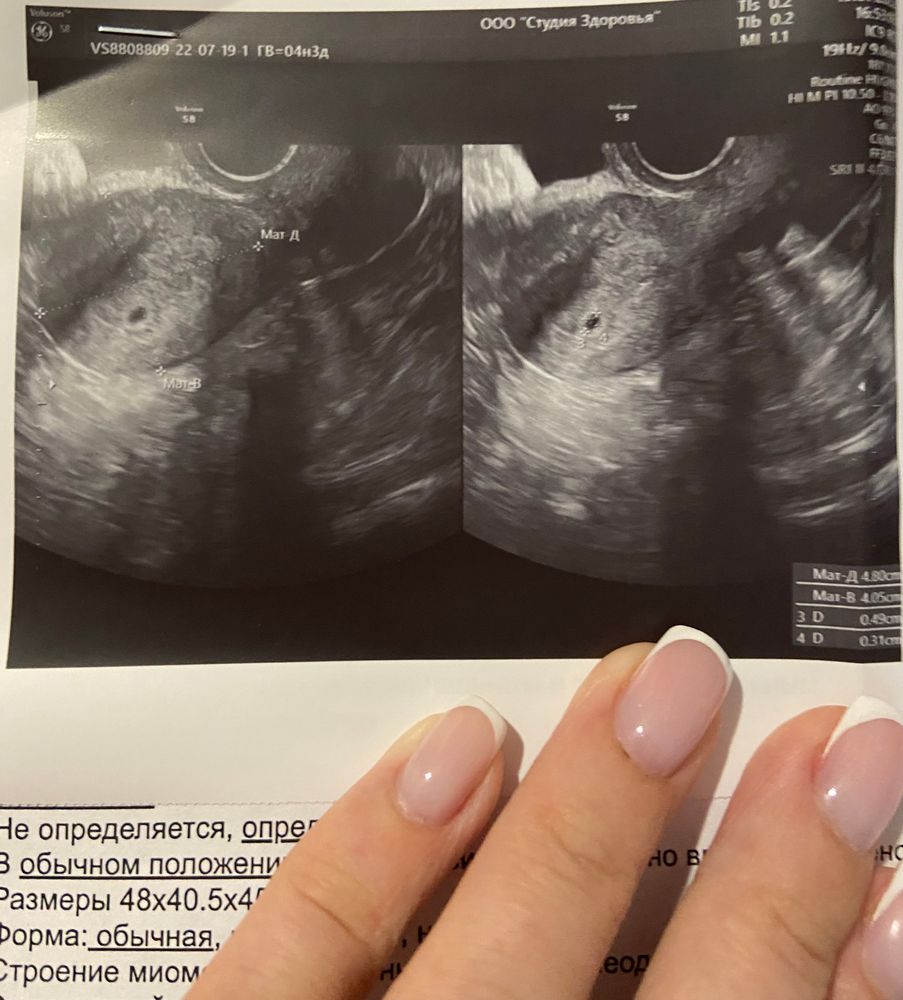

И вечером приходит результат хгч: 112. Через день 256, ещё через день 624. Жду 19 числа и еду на узи, подтвердить беременность и вот:

Сейчас у меня 11 неделя, 12 сентября первый скрининг..